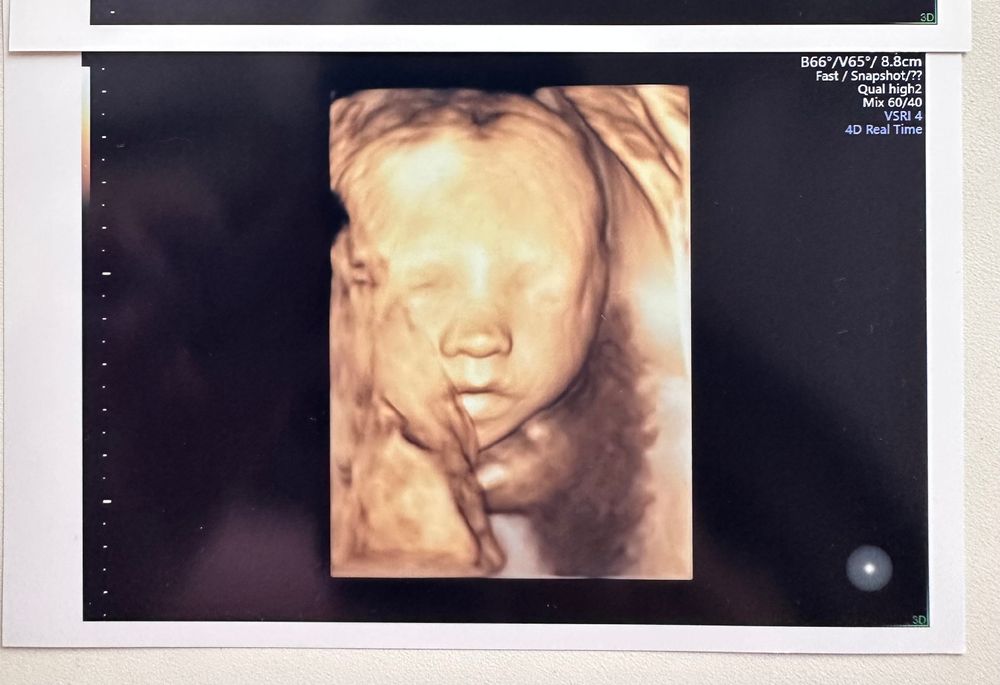

4D узи в 26 недель и 6 дней 🫶🏼💓

Урааа, в эту беременность малышка повернулась личиком и полностью дала себя обсмотреть ☺️

Очень хотела посмотреть на носик, т.к гипоплазия и размер косточек очень маленький.

Весит малышка примерно 913 грамм 💟